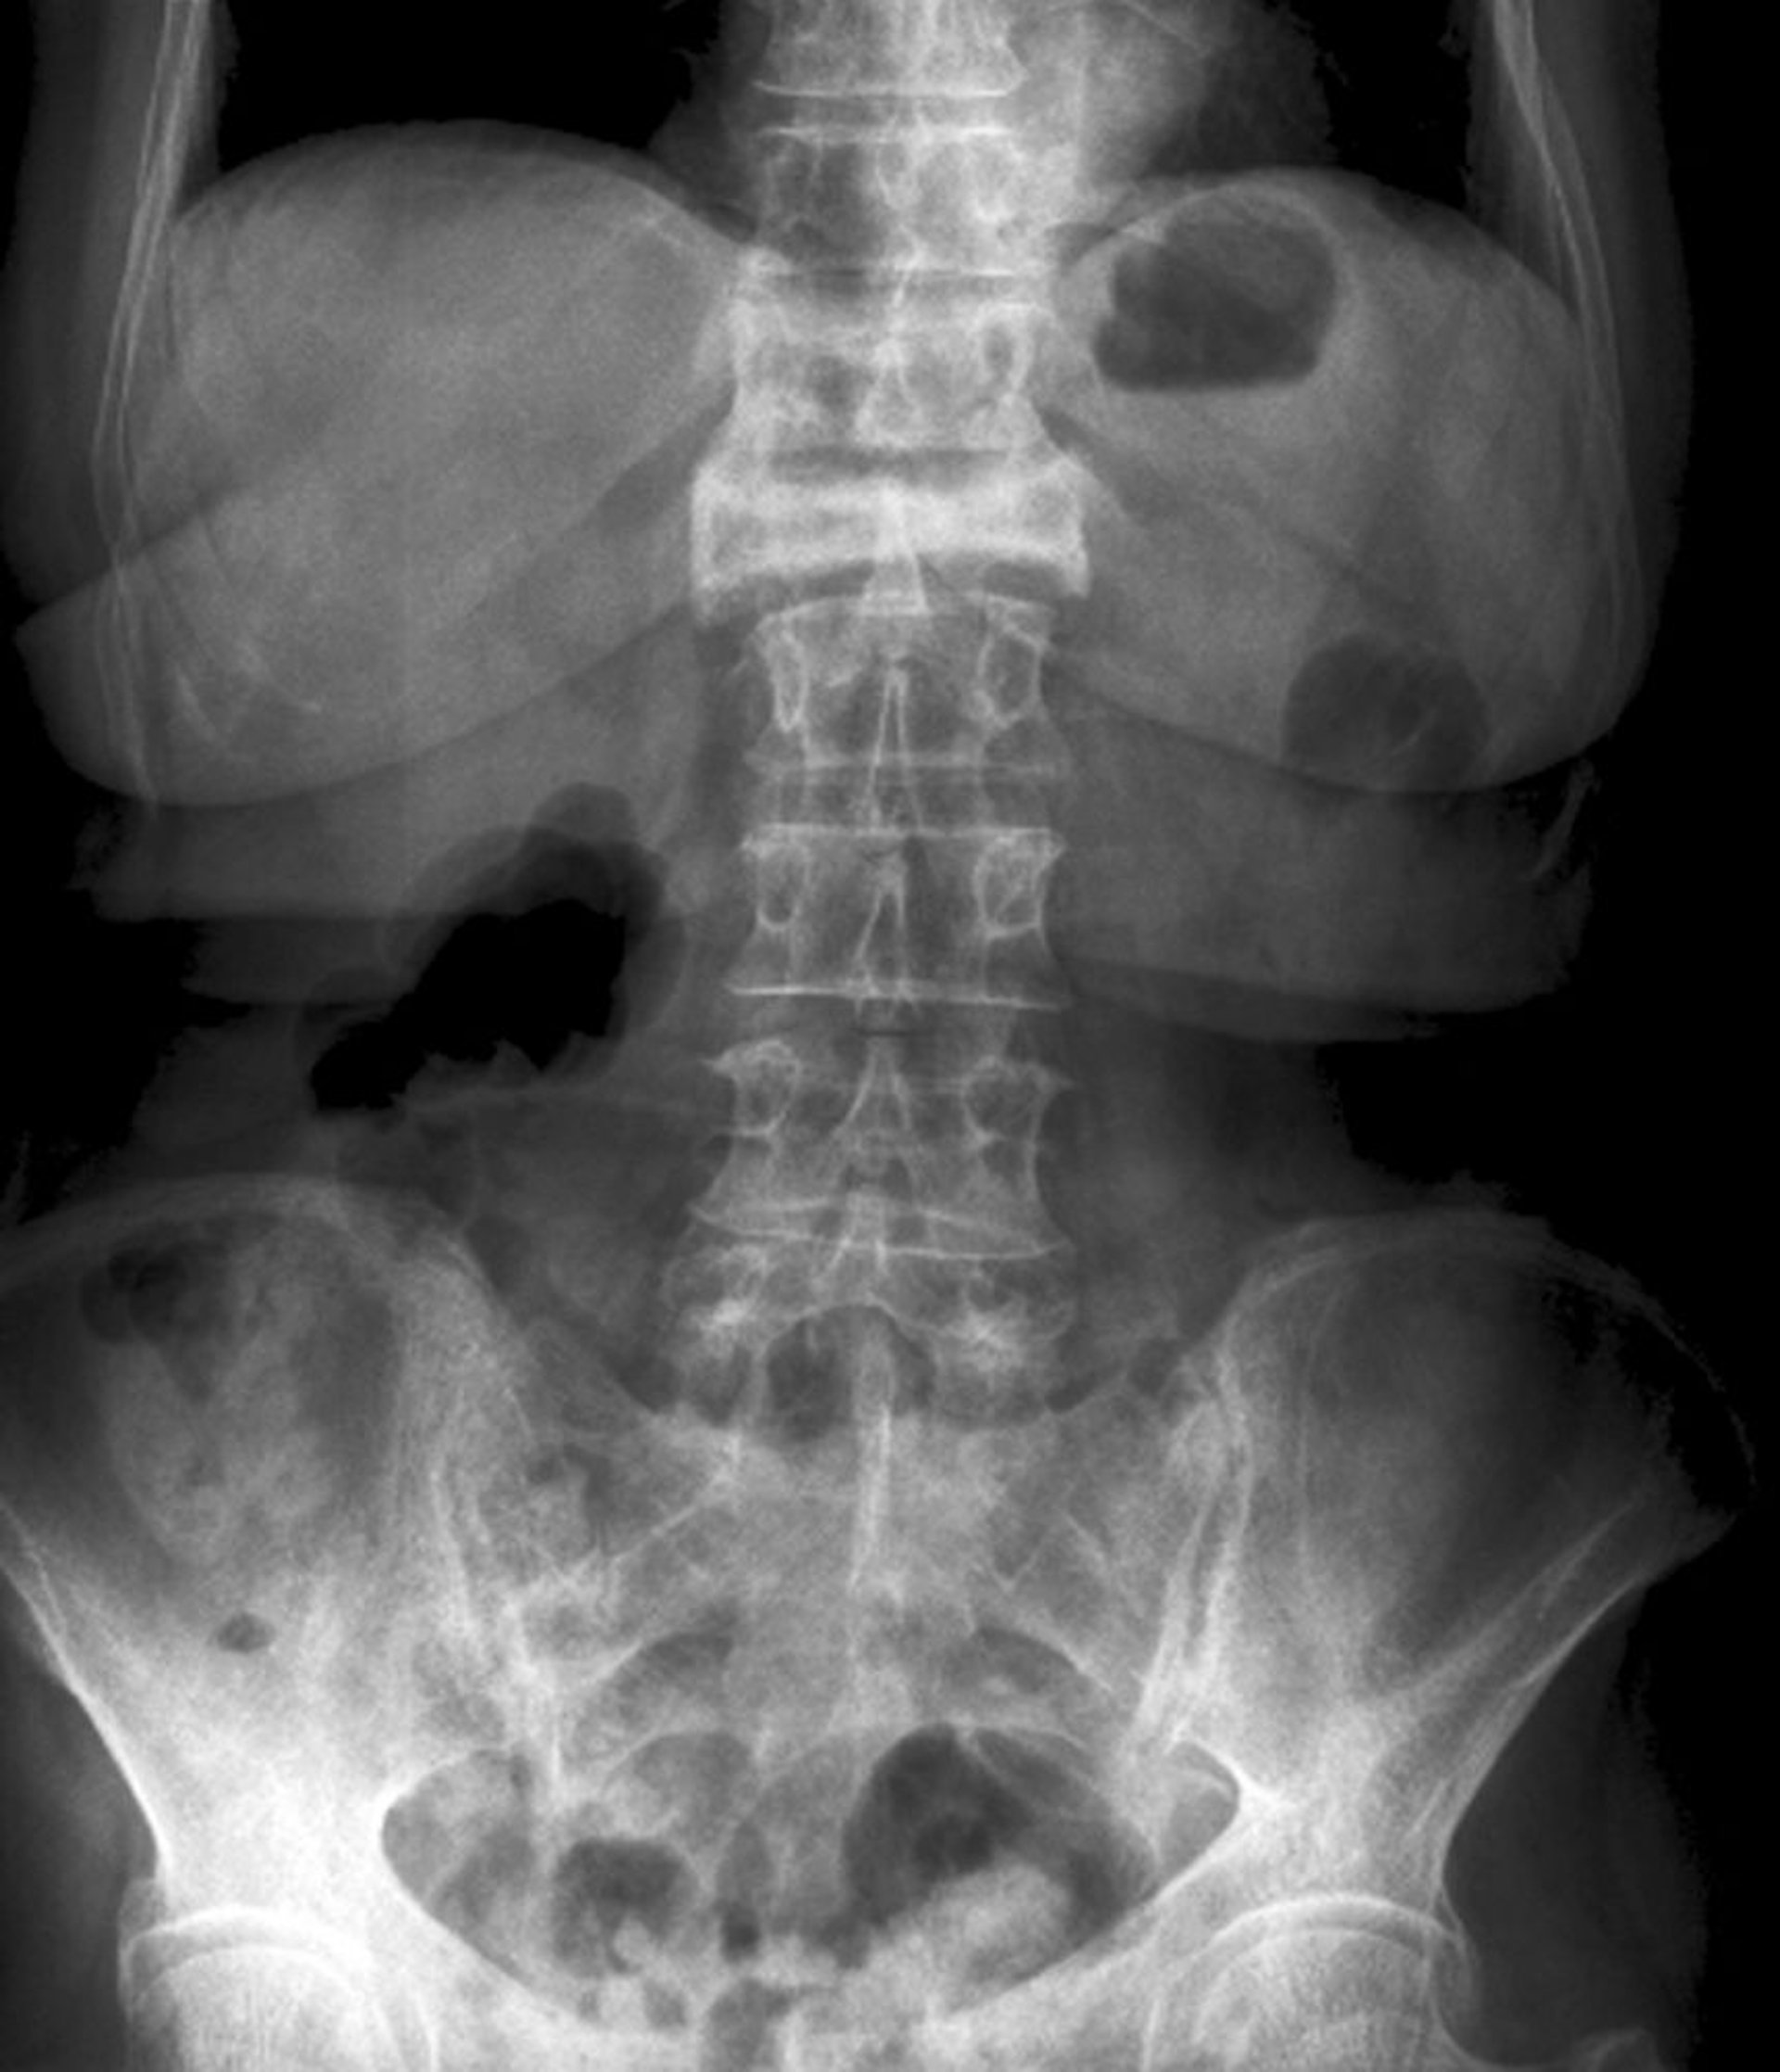

Incidence de face d'une fracture par compression (tassement) sévère

Cette fracture par compression (tassement) de la 1ère vertèbre lombaire est visible en incidence de face sous la forme d'une perte sévère de hauteur et d'une augmentation de la radiodensité.

ZEPHYR/SCIENCE PHOTO LIBRARY